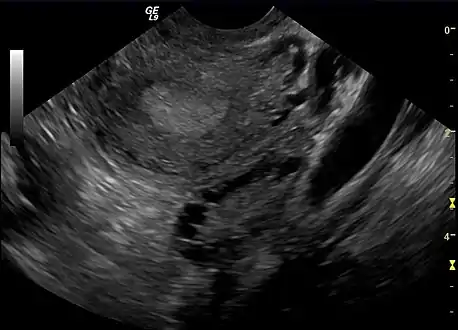

Transvaginal ultrasound scan of polycystic ovary

Transvaginal ultrasound scan of polycystic ovary Polycystic ovary as seen on sonography

Polycystic ovary as seen on sonography

The syndrome acquired its most widely used name due to the common sign on ultrasound examination of multiple (poly) ovarian cysts. These "cysts" are in fact immature ovarian follicles. The follicles have developed from primordial follicles, but this development has stopped ("arrested") at an early stage, due to the disturbed ovarian function. The follicles may be oriented along the ovarian periphery, appearing as a 'string of pearls' on ultrasound examination.[86]

- Gynecologic ultrasonography, specifically looking for small ovarian follicles. These are believed to be the result of disturbed ovarian function with failed ovulation, reflected by the infrequent or absent menstruation that is typical of the condition. In a normal menstrual cycle, one egg is released from a dominant follicle – in essence, a cyst that bursts to release the egg. After ovulation, the follicle remnant is transformed into a progesterone-producing corpus luteum, which shrinks and disappears after approximately 12–14 days. In PCOS, there is a so-called "follicular arrest"; i.e., several follicles develop to a size of 5–7 mm, but not further. No single follicle reaches the preovulatory size (16 mm or more). According to the Rotterdam criteria, which are widely used for diagnosis of PCOS,[10] 12 or more small follicles should be seen in a suspect ovary on ultrasound examination.[21] More recent research suggests that there should be at least 25 follicles in an ovary to designate it as having polycystic ovarian morphology (PCOM) in women aged 18–35 years.[95] The follicles may be oriented in the periphery, giving the appearance of a 'string of pearls'.[96] If a high-resolution transvaginal ultrasonography machine is not available, an ovarian volume of at least 10 ml is regarded as an acceptable definition of having polycystic ovarian morphology. rather than follicle count.[95]

Ultrasound findings in PCOS include enlarged ovaries with peripheral follicles in a "string of pearls" configuration.